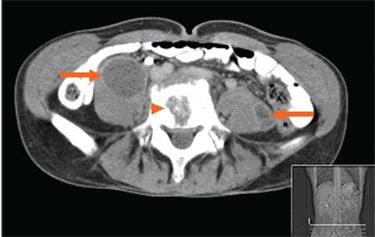

Abdominal CT findings included multiple retroperitoneal and paravertebral abscesses (arrows) and osteomyelitis of the L4 vertebral body (arrowhead). Intravenous cefotaxime and metronidazole were started.